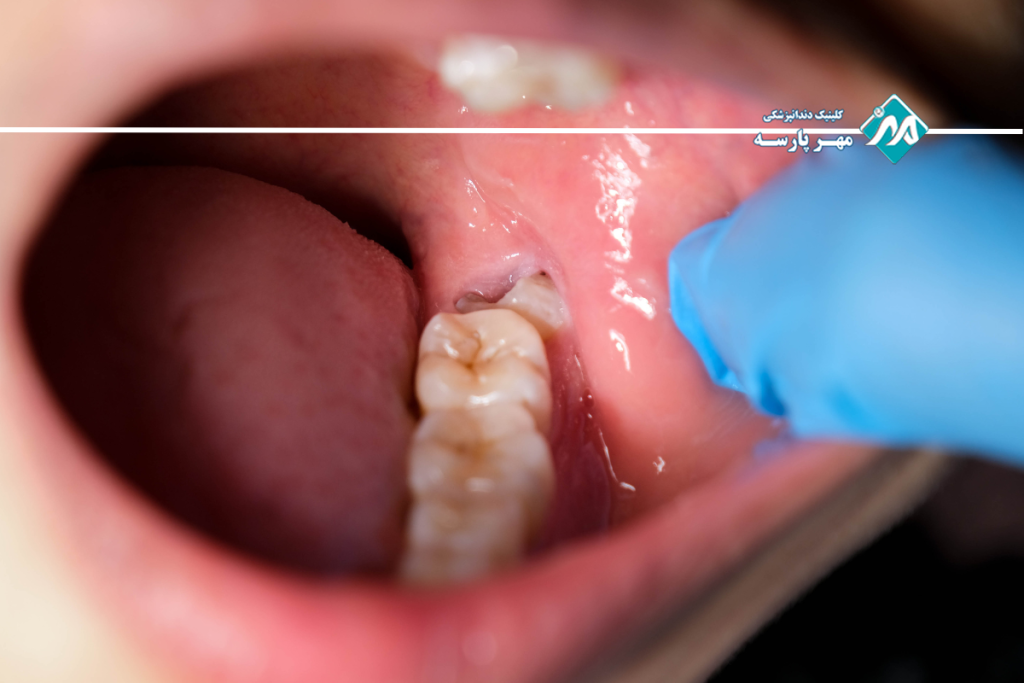

اجسام خارجی گیر کرده در لثه

یکی از آسیبهای رایج لثه، گیرکردن اجسام خارجی در فضای بین لثه و دندان است. پوسته پاپکورن، تکههای کوچک استخوان یا فیبرهای سفت مواد غذایی میتوانند در این ناحیه گیر کنند و باعث التهاب و سپس عفونت شوند.

آبسه پریودنتال یا عفونت لثه – وقتی التهاب به بحران میرسد

آبسه پریودنتال (Periodontal Abscess) نوعی کیسه پر از چرک و عفونت است که در بافت لثه ایجاد میشود. این عارضه معمولاً باعث درد متوسط تا شدید میشود و نیاز به درمان فوری دارد.

دلایل شایع ایجاد آبسه لثه عبارتاند از:

گیرکردن اجسام خارجی زیر لثه

بیماریهای پیشرفته لثه (پریودنتیت) که کنترل نشدهاند

این مشکل معمولاً ناگهانی بروز میکند و درد آن میتواند شبیه دنداندرد شدید باشد. فشار چرک در ناحیه عفونی، تورم و حساسیت را افزایش میدهد. از دیگر علائم آبسه میتوان به نبضدار بودن محل، قرمزی، تورم، تب و بوی بد دهان اشاره کرد.